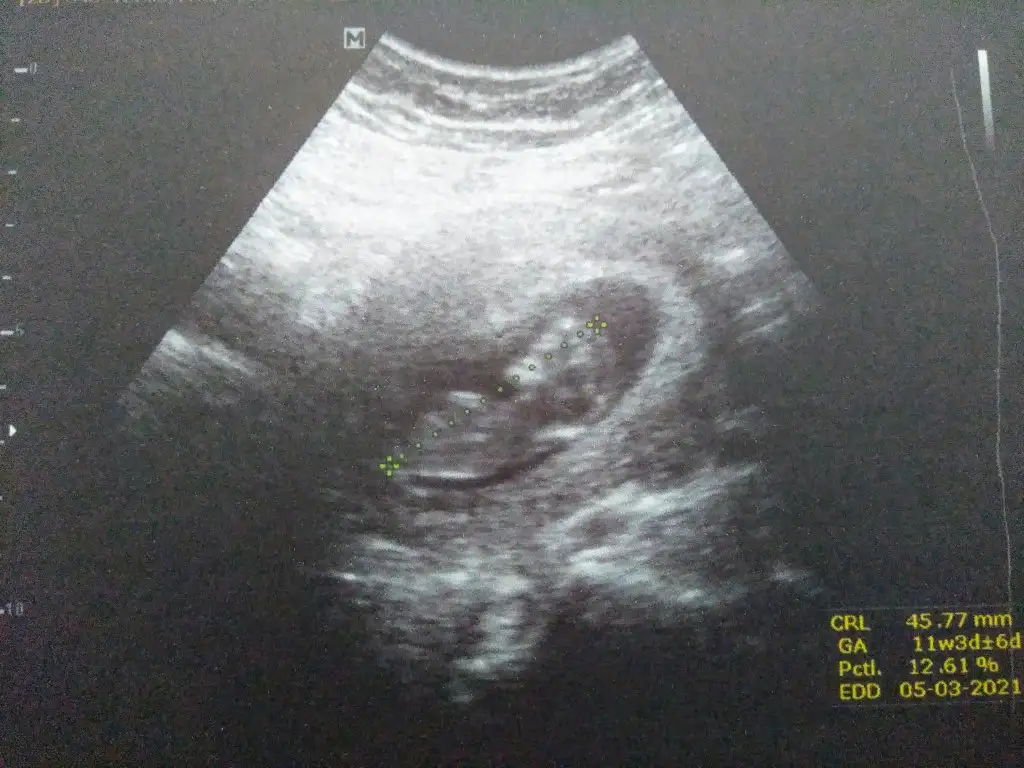

Sanki erkek gibi emin olamadım Dr + getirmiş nubuna çok zor tahmin etmek 12-13 hafta olursa paylasinKızlar benim bebeğimin cinsiyetinide tahmin eder misiniz 11+3te cekildi. Ve aynı gün kalp atisida 168 geldi.Eki Görüntüle 2677122

Merhaba banada yorum yapar mısınız. 11+4 de çekildi

Kız gibi sanki 13 hafta olursa paylaşın çok net değil USGIkra meyra canım yorumlar mısın